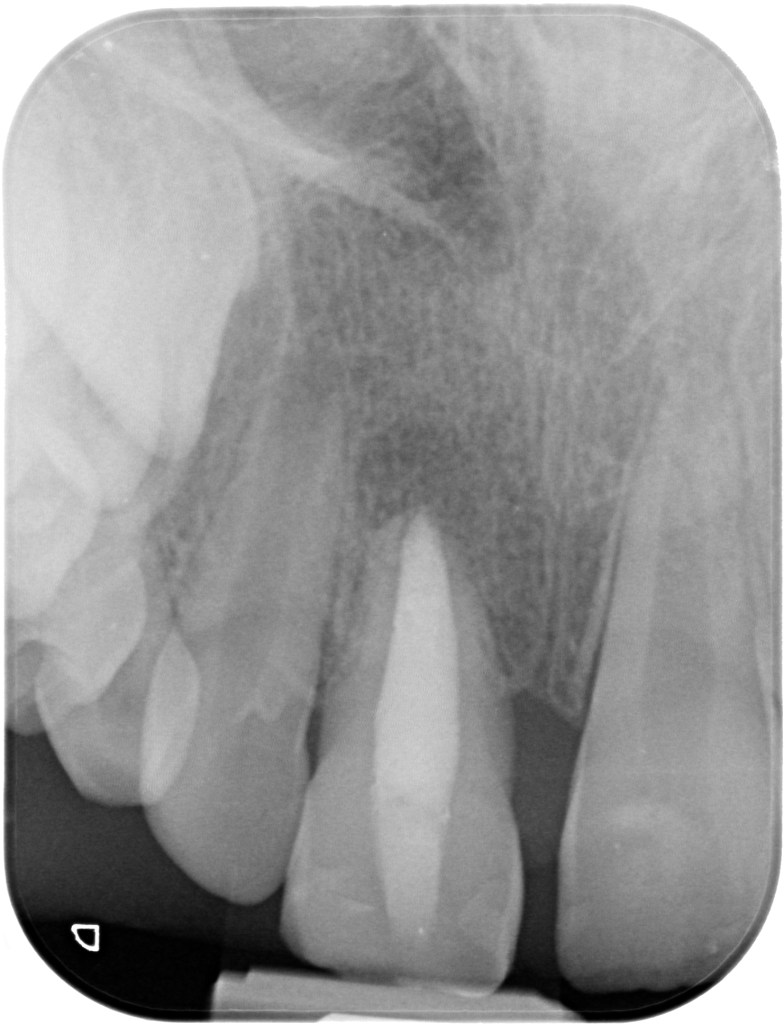

07.12.2023 Patient LS, geb. am 08.10.2014, Zahn 11 (Zustand nach Trauma, apikale Aufhellung, weit offenes Foramen apicale)